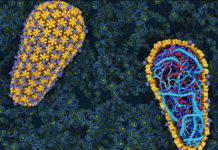

Los pacientes con VIH / SIDA tienen un riesgo significativamente mayor de muerte súbita cardíaca (MSC), según un estudio publicado en el 22 de mayo de la revista Journal de la American College of Cardiology.

VIH Podría Aumentar Riesgo De Muerte Cardíaca Súbita